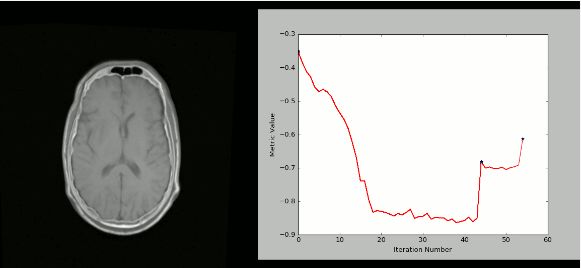

8. SimpleITK

ITK(Insight Segmentation and Registration Toolkit)是一个“开源,跨平台系统,为开发人员提供了一套用于图像分析的广泛软件工具。SimpleITK是一个基于ITK构建的简化层,旨在促进其在快速原型设计,交易以及解释语言方面的应用。”它也是一个图像分析工具包,具有大量组件,支持一般过滤操作,图像分割和配准。SimpleITK是用C ++编写的,但它可用包括Python在内的大量编程语言进行操作。

资源

有大量的Jupyter Notebook说明了SimpleITK在教育和研究活动中的应用。Notebooks使用Python和R编程语言演示如何使用SimpleITK进行交互式图像分析。

用法

使用SimpleITK和Python创建可视化的严格CT / MR配准过程: